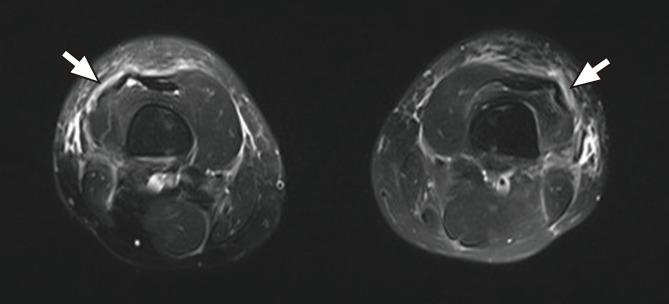

Eosinophilic fasciitis is a rare disease characterized by diffuse fasciitis with peripheral eosinophilia and progressive induration and thickening of the skin and soft tissues. We report a 19-year-old female who presented with pitting edema in both lower extremities. She had a history of excessive physical activity before her symptoms developed. Physical examination revealed 2+ pitting edema in both lower legs. She complained of mild pain in both knee joints and feet, with no tenderness or heating sensations. Laboratory results were unremarkable except for severe eosinophilia. Parasite infection, venous thrombosis, and cardiac and renal problems were excluded. A magnetic resonance imaging study of both lower extremities revealed increased signal intensity in the subcutaneous lesions, consistent with superficial inflammation of the fascia. Mixed perivenular lymphoplasmacytic and eosinophilic infiltration in the subcutaneous lesion were observed on biopsy. The patient was treated with corticosteroids, resulting in remarkable improvement in both edema and eosinophilia.

嗜酸性筋膜炎是一种罕见疾病,其特征为弥漫性筋膜炎伴外周血嗜酸性粒细胞增多,以及皮肤和软组织的进行性硬化和增厚。我们报告了一例 19 岁女性患者,其双侧下肢出现凹陷性水肿。她在出现症状前有过度体力活动的病史。体格检查发现双小腿有 2+凹陷性水肿。她主诉双膝和双脚轻度疼痛,无触痛或发热感。实验室结果除了严重的嗜酸性粒细胞增多外无其他异常。寄生虫感染、静脉血栓形成以及心脏和肾脏问题均已排除。双下肢磁共振成像显示皮下病变的信号强度增加,符合筋膜浅表炎症。活检显示皮下病变中混合性小静脉旁淋巴浆细胞和嗜酸性粒细胞浸润。该患者接受了皮质类固醇治疗,水肿和嗜酸性粒细胞增多均显著改善。